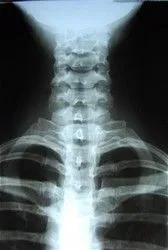

X-Ray

X-rays are taken at our facility. Depending on the findings, the chiropractor may call for an MRI or other imaging study.